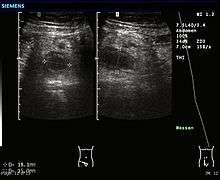

Ultrasonography and Doppler sonography are useful to detect appendicitis, especially in children. Ultrasound can show free fluid collection in the right iliac fossa, along with a visible appendix with increased blood flow when using color Doppler, and noncompressibility of the appendix, as it is essentially a walled off abscess. Other secondary sonographic signs of acute appendicitis include the presence of echogenic mesenteric fat surrounding the appendix and the acoustic shadowing of an appendicolith.[45] In some cases (approximately 5%),[46] ultrasonography of the iliac fossa does not reveal any abnormalities despite the presence of appendicitis. This false negative finding is especially true of early appendicitis before the appendix has become significantly distended. In addition, false negative findings are more common in adults where larger amounts of fat and bowel gas make visualizing the appendix technically difficult. Despite these limitations, sonographic imaging in experienced hands can often distinguish between appendicitis and other diseases with similar symptoms. Some of these conditions include inflammation of lymph nodes near the appendix or pain originating from other pelvic organs such as the ovaries or Fallopian tubes.